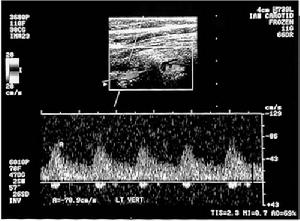

椎動脈造影是椎動脈型頸椎病的檢查方法之一。一般用於臨床上考慮為椎動脈型頸椎病,但並不十分肯定;或者當椎動脈型頸椎病保守治療無效,準備施行手術治療時,應當進行椎動脈造影,以明確椎動脈是否因椎間盤突出,鉤椎關節骨刺的壓迫或刺激,造成了椎動脈的扭曲、痙攣、變細、梗阻,或者椎動脈有無畸形及動脈硬化等,另外還可以觀察椎動脈的異常改變與頸椎活動的關係。

目前的椎動脈造影方法,大多採用從椎動脈以外的動脈穿刺插管,在電視透視監視下將插管送至椎動脈,然後注入含碘的造影劑,同時進行動態的透視觀察或者拍攝X線片。也可以在頸部向各個方向活動時,進行動態的透視觀察或者拍攝X線片,以明確椎動脈是否有扭曲、痙攣、變細、梗阻或者椎動脈有無畸形及動脈硬化等,以及椎動脈的異常改變與頸椎骨刺和頸椎活動的關係。

椎動脈造影併發症較多,包括局部血管損傷、出血、感染、全身性過敏反應以致過敏性休克甚至死亡。由於造影劑對椎動脈的刺激,導致椎動脈的痙攣引起一過性腦部缺血的症狀,包括暫時性運動障礙、視力障礙以及頭暈等。椎動脈刺激引起腦部的併發症與造影劑的濃度有關,濃度越高併發症越常見。由於無創性的核磁共振椎動脈顯影技術的出現,其椎動脈顯影清楚,而且為無創性檢查。核磁設備對於軟傷科治療頸椎病,尤其是頸椎椎管狹窄、椎動脈型頸椎病的檢查上可以取代椎動脈造影。